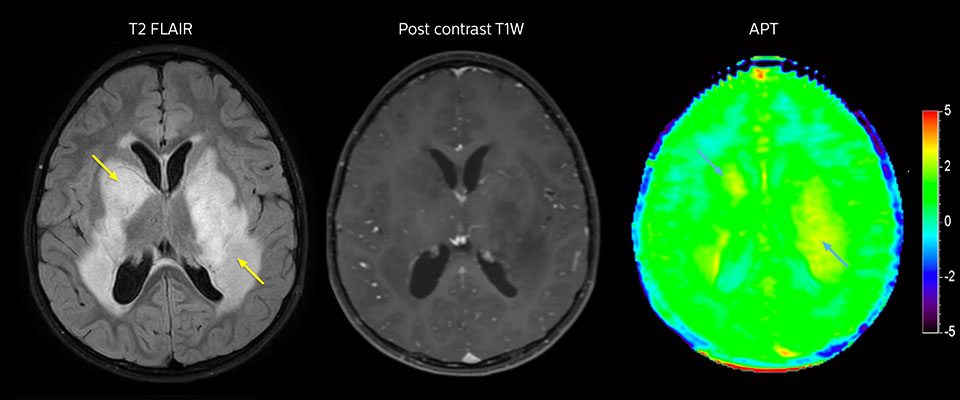

APT may illuminate post-resection images with crucial information

MRI may be performed after tumor resection, to look for residual tumor or tumor regrowth. Also here, the different contrast mechanism of APT may help in diagnosis. Dr. Miller remembers a particular case.

“After a very good resection, we saw small changes on the postcontrast T1-weighted and the T2-weighted images that looked like a post-surgical little bit of fluid. Interestingly, however, we saw a focal area of APT signal, right in the center of that abnormality. As we usually do when a bit unsure, we followed it up and, unfortunately, found tumor regrowth in that region,” Dr. Miller says. “Cases like this motivate me, and others who care about this population, to investigate how this APT method could be used on large scale in this population and help us in providing high value diagnostic information.”

The hospital’s physicians also saw a case where APT had a negative predictive value. Following the resection of a highgrade tumor, they saw a similar small change in the images of this patient. However in this case, the APT signal was rather low. In a recent rescanning of this patient, no recurrence was seen.

MRI with APT post resection

Immediately post resection MRI was again performed. T2-weighted and postcontrast T1-weighted images are quite inconclusive for distinguishing residual tumor tissue from postoperative tissue changes. On the APT image some high signal is still seen, which would suggest residual tumor tissue.

Follow-up over time results

Follow-up over time

In later follow-up scans the post-contrast T1-weighted images suggest recurrent tumor growth. So, it would be interesting to study the predictive value of APT in a large patient group.